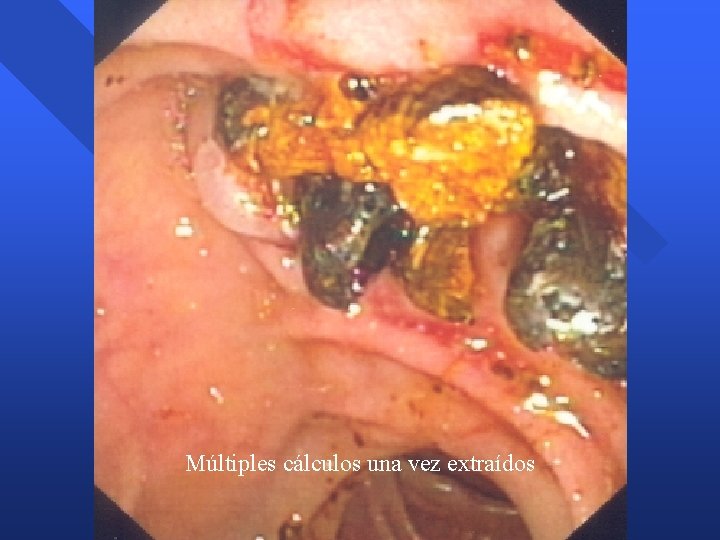

Múltiples cálculos una vez extraídos